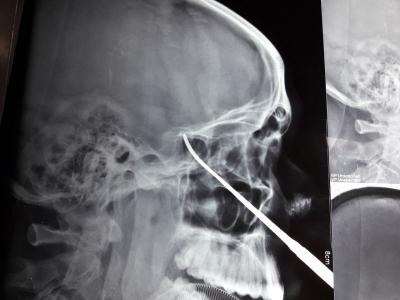

أجرى فريق طبي اختصاصي في مستشفى ابن سينا التعليمي/ الموصل عملية جراحية نوعية للغده النخامية المفرزة لهرمون الحليب غير المستجيب للعلاج عن طريق الأنف لمريضة في عقدها الرابع باستخدام أحدث ناظور للدماغ، وذلك يوم الاثنين 29 نيسان 2019. وتألف الفريق الطبي من كل من الأستاذ المساعد الدكتور هيثم عبدالملك النوري (تدريسي شعبة الانف والأذن والحنجرة فرع الجراحة كلية الطب جامعة الموصل)، وبمعيته كل من الجراح الاختصاص الدكتور محمد نذير الزبيدي اختصاص الجراحة العصبية وفريق التخدير بقياده الدكتور محمد ذنون ومساعد مخدر ايمن لقمان و ياسر احمد ومساعد جراح ياسر فتحي ومسؤول صالة العمليات علي اسماعيل (وهم من دائرة صحة نينوى). ولله الحمد، فقد تكللت العملية بالنجاح بعدما اخضعت المريضة الى وحدة العناية الفائقة وتلقت العلاج اللازم. وتمت متابعة حالة المريضة لحين خروجها، وهي تنعم بالصحة والعافية، حيث عاد الهرمون الى مستواه الطبيعي.. مبارك للدكتور النوري هذا التألق والعطاء، ومن الله التوفيق.